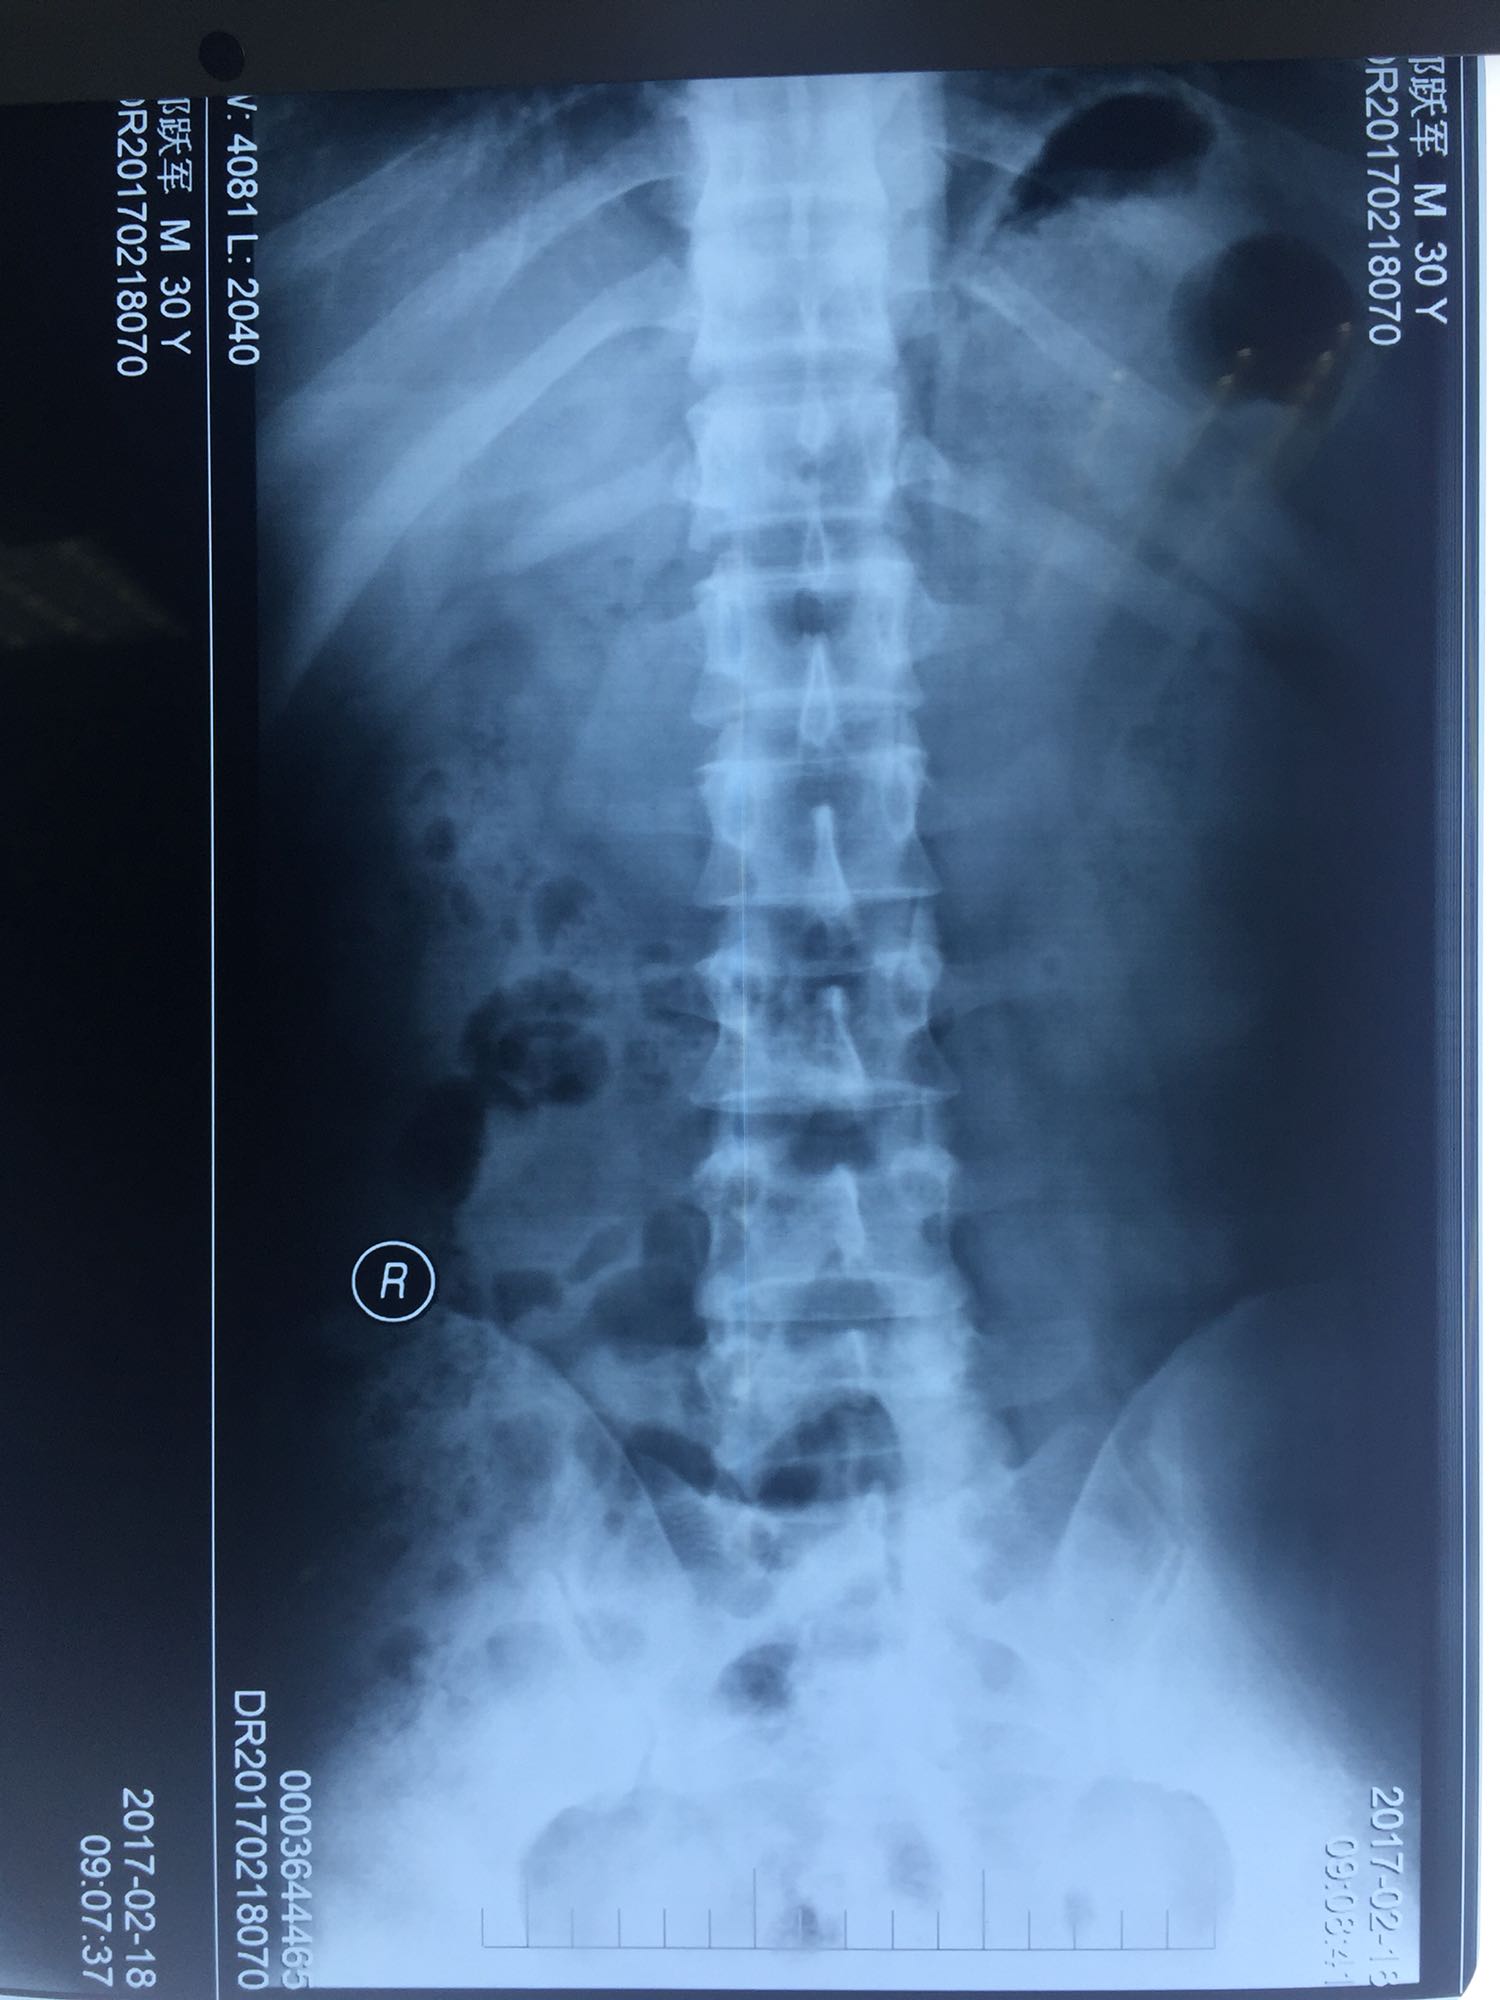

腰骶部肌紧张,腰5骶1棘间及左侧椎旁有压痛及放散痛,左侧坐骨神经出孔处有压痛及放散痛,左侧足背外侧及足底部皮肤感觉麻木,左侧直腿抬高试验阳性(30度)。

诊断:腰5骶1椎间盘突出症 治疗方案:椎间孔镜下经椎板间入路髓核摘除术